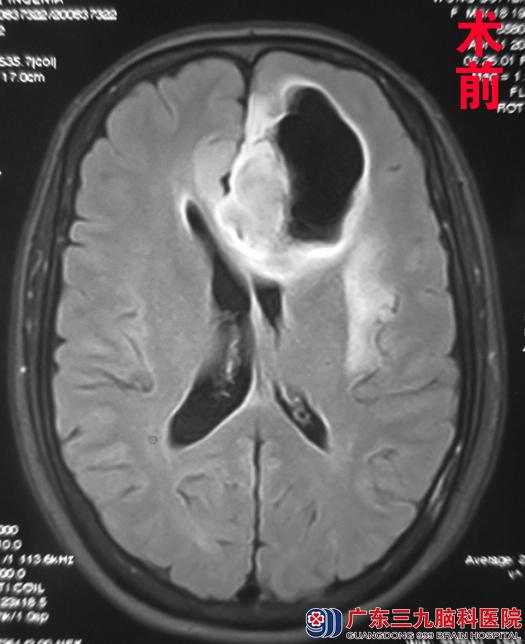

为求进一步治疗,黄女士经朋友介绍来到广东三九脑科医院综合神经外科(神经外五科)求治。入院头颅磁共振检查见:左侧额叶占位,大小约3.76 cm×5.55 cm×4.07cm。完善相关检查后,外五科鲁明主任主刀,在唤醒麻醉下为其行左侧额叶占位切除术+颅内压探头置入术。术中采用导航定位,用电生理探查术区皮层功能,术中显微镜下见白色肿瘤组织,血供一般,边界不清,在患者语言、运动配合正常下,全切肿瘤,手术顺利结束。术后黄女士未出现语言及肢体功能障碍,顺利康复。术后病理结果:少突胶质细胞瘤(WHO II级)。